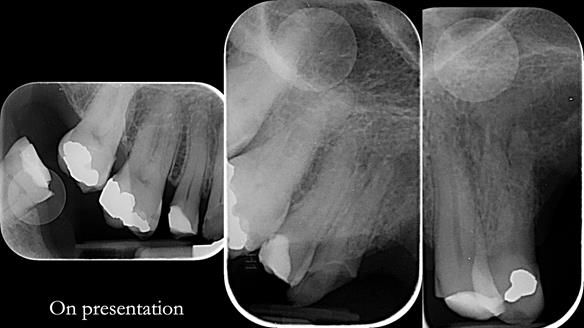

Keith’s case was one of the most challenging and rewarding cases I’ve treated this year. This 64 year old man presented with ill-fitting acrylic partial dentures that lacked stability, retention, and aesthetics. They constantly broke. He had lost the upper front teeth in a road traffic accident in his early 20s. The unopposed teeth had erupted, taking up space. After careful planning, we made a durable, metal-based upper partial denture/splint to address his dental concerns. He loved the outcome.

1. Denture design: A custom cobalt-chromium framework was Scandinavian-designed to maximise stability, protect the remaining teeth, and allow for future additions if needed.

2. Onlay preparations: Composite onlays were fitted for his upper left premolars to repair these teeth and support the new denture.

Keith’s denture incorporated a Duracetal shell clasp on upper right first premolar (Myerson), which are designed to be virtually visible, providing a more aesthetic solution while enhancing patient comfort. The Scandinavian-inspired approach, based in modern removable prosthodontic techniques, ensured the denture was not only durable but also visually pleasing. Additionally, the design was carefully planned to allow for future modifications, ensuring that if Keith loses additional teeth, the denture can be adapted rather than replaced entirely.

I also used the Dahl concept to re-establish the occlusion upon fitting the RPD, which helped to intrude the lower left canine without needing to grind it too much.